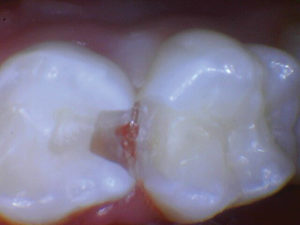

Caso 3

La caries recurrente en un diente primario que involucra múltiples superficies generalmente conduce a una cobertura total y con razón. Sabemos que los materiales a base de resina tienen fugas en ambientes hostiles ácidos y acribillados de sacarosa; por lo tanto, se recomienda una cobertura total en estos casos. ¿Qué pasaría si pudiéramos restaurar con un material más estético para los padres estéticos? En estos casos estéticos, todavía necesitamos resistencia y un material activo no inerte.

Figura 1. Fotografía preoperatoria del segundo molar primario superior derecho con caries distoocluso-bucal. En el pasado, al menos para mí, el tratamiento habría sido una corona de cobertura total (probablemente de acero inoxidable). Debido a las preocupaciones estéticas de los padres, es bueno tener una opción alternativa, especialmente un material que sea activo dentro del entorno oral. |

Figura 2. La caries se excavó y se eliminó todo el esmalte socavado. |